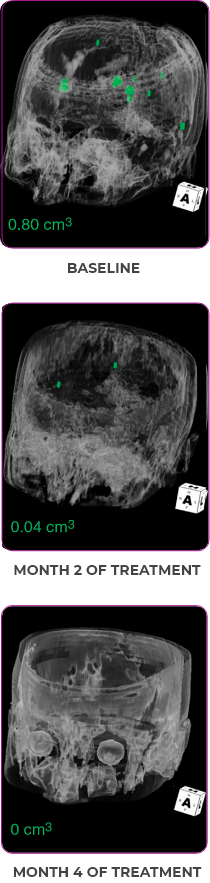

PATIENT CASE:

METASTATIC, RAIa-REFRACTORY,

PAPILLARY THYROID CANCER1

- 56-year-old female with PTCa that had metastasized to multiple sites, including the brain

- Progression after first- and second-line systemic treatment

- PRa after 4 weeks on VITRAKVI® (larotrectinib); CRa after 8 weeks

- At last assessment, complete response was sustained over an 11-month period

Response to VITRAKVI1

- After 8 weeks on VITRAKVI, all target lesions had disappeared, demonstrating a complete response

- The complete response was sustained over 11 months of treatment with VITRAKVI

- Patient experienced Grade 1 fatigue and mild hepatic enzyme elevation

Response in primary and metastatic lesions1

MRIa imagery of the lungs. Arrow indicates large target lesion in left lung.1

SCAN 1: LUNG

MRIa imagery of the brain. Arrow indicates large target lesion in left lung.1

aMRI, magnetic resonance imaging.